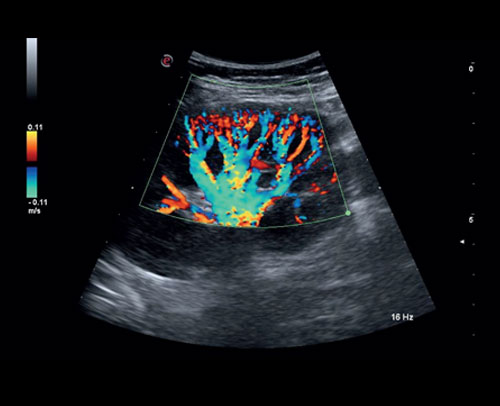

Perfuze ledvin s vysoce citlivým režimem Color Doppler.

Fetální Willisův kruh s Power Dopplerem.